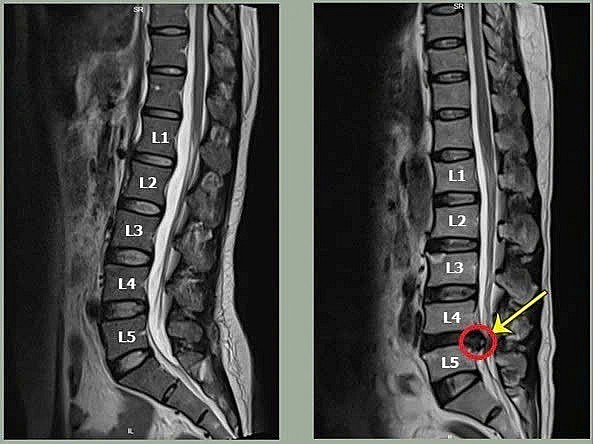

| Hình ảnh bệnh nhân bị thoát vị đĩa đệm cột sống từ L2-L5. Ảnh: Nguồn internet |

Thoát vị đĩa đệm xảy ra khi nhân nhầy bên trong đĩa đệm thoát ra ngoài, chèn ép vào rễ thần kinh hoặc tủy sống. Tình trạng này thường biểu hiện bằng những cơn đau buốt vùng thắt lưng, lan xuống mông và chân, khiến việc đi lại trở nên khó khăn.

Điều đáng sợ của thoát vị đĩa đệm không nằm ở những cơn đau ban đầu, mà ở diễn tiến âm thầm của bệnh. Khi không được điều trị đúng cách, khối thoát vị có thể ngày càng lớn, làm tăng áp lực lên dây thần kinh.

Hậu quả là tình trạng yếu cơ, teo cơ xuất hiện. Nếu kéo dài, người bệnh có thể mất dần khả năng vận động, thậm chí đối mặt với nguy cơ liệt một biến chứng nặng nề ảnh hưởng trực tiếp đến chất lượng cuộc sống và khả năng lao động.